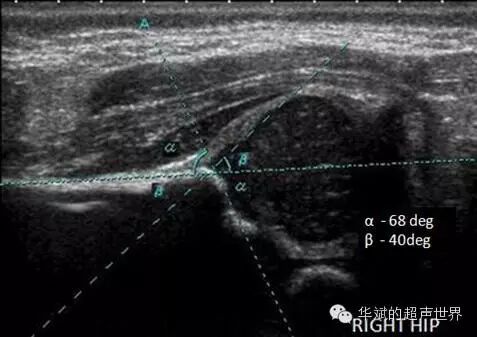

但是,对于未成熟髋关节的测量颇多争议(图4)。α角的测量没有争议,都认为骨性髋臼顶线是由图中的软骨性髋臼顶与骨性髋臼顶的分界点(图4中1点处)与3点之间的连线。按照Graf本人的主张,唇线应该是图4中1点处与2点之间的连线。但是这样测量的结果会把导致β角测值严重畸大,结果使得很多仅仅是未成熟的髋臼被误判为异常髋臼,假阳性率极高。为了减低假阳性率,因此很多研究者不赞同Graf本人关于未成熟髋的唇线测量方法,而采用髋顶线与髂骨线的交点(图4中的4点处)到唇缘(2点处)的连线为唇线。

图4 未成熟髋关节的不同测量方法

图5 Graf主张的未成熟髋的α角与β角的测量。

正是因为关于唇线的画法存在差异,造成不同研究者关于β角的意义的差异很大,因此很多指南中索性摒弃了β角,而只推荐测量α角作为髋臼分型的依据。我们工作中也是以α角为主要参考,并结合动态检查做出判断,β角一般可以忽略。